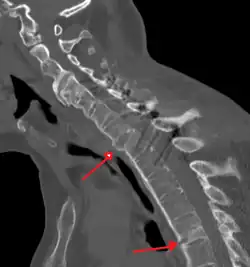

Lateral X-ray of the neck in ankylosing spondylitis -

CT scan showing bamboo spine in ankylosing spondylitis -